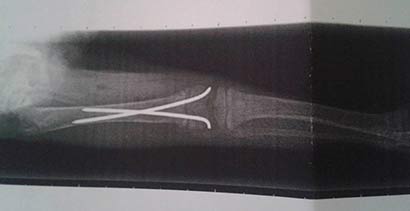

Das kleine Fellbündle wurde gefunden und ins Tierheim gebracht (und leider nicht wieder abgeholt), dort stellte man fest, dass er schreckliche Schmerzen im hinteren Bereich hatte. Um dem hübschen Bub Erleichterung verschaffen zu können, wurde er gleich dem Tierarzt vorgestellt. Leider gab es dort keine guten Neuigkeiten, er hatte sich einen schweren Bruch des Oberschenkels zugezogen, welcher sofort operiert werden musste.